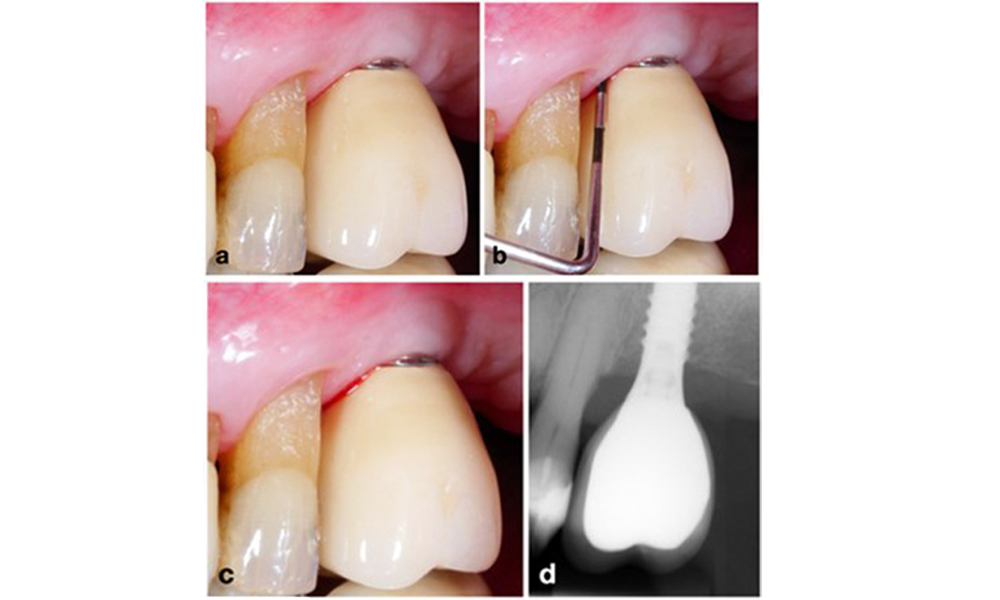

Auf dem World Workshop on the Classification of Periodontal and Peri‐Implant Diseases and Conditions 2017 wurden diagnostische Kriterien für periimplantäre Mukositis und Periimplantitis festgelegt (Renvert et al. 2018). Periimplantäre Mukositis ist definiert als (1) Entzündung um das Implantat (also Rötungen, Schwellungen, Blutfäden oder Blutstropfen innerhalb von 30 Sekunden nach dem Sondieren), jedoch (2) ohne zusätzlichen Knochenverlust nach der Ersteinheilung (Abb. 1).

Periimplantitis ist zu erkennen an (1) Entzündungszeichen, vergleichbar einer Mukositis, (2) einem radiologischen Nachweis von Knochenverlust nach Ersteinheilung und (3) der Zunahme der Sondierungstiefe im Vergleich zu Messungen kurz nach dem Einsetzen der prothetischen Rekonstruktion (Abb. 2). Liegen keine früheren Röntgenaufnahmen vor, weisen ein radiologisches Knochenniveau von ≥ 3 mm zusammen mit Sondierungsblutungen und Sondierungstiefen von ≥ 6 mm auf eine Periimplantitis hin.